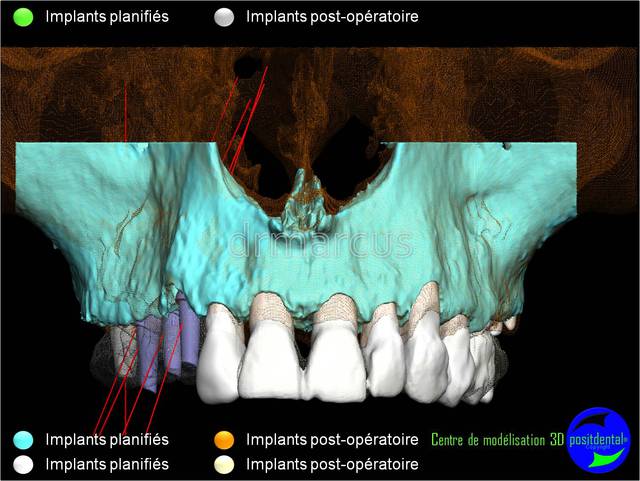

Analyse post-opératoire d’une MCI post-extractionnelle en chirurgie guidée

Cas clinique de drmarcus

Chirurgie : drmarcus

Imagerie 3D: POSITDENTAL

Dommage que ce soit scanner avant et Cone-Beam après. Il est vrai que l’interprétation peut différer. Toutefois on voit la parfaite superposition des implants entre la planification et la réalisation. J'en conclue que le système Positdental est relativement fiable ;-))))